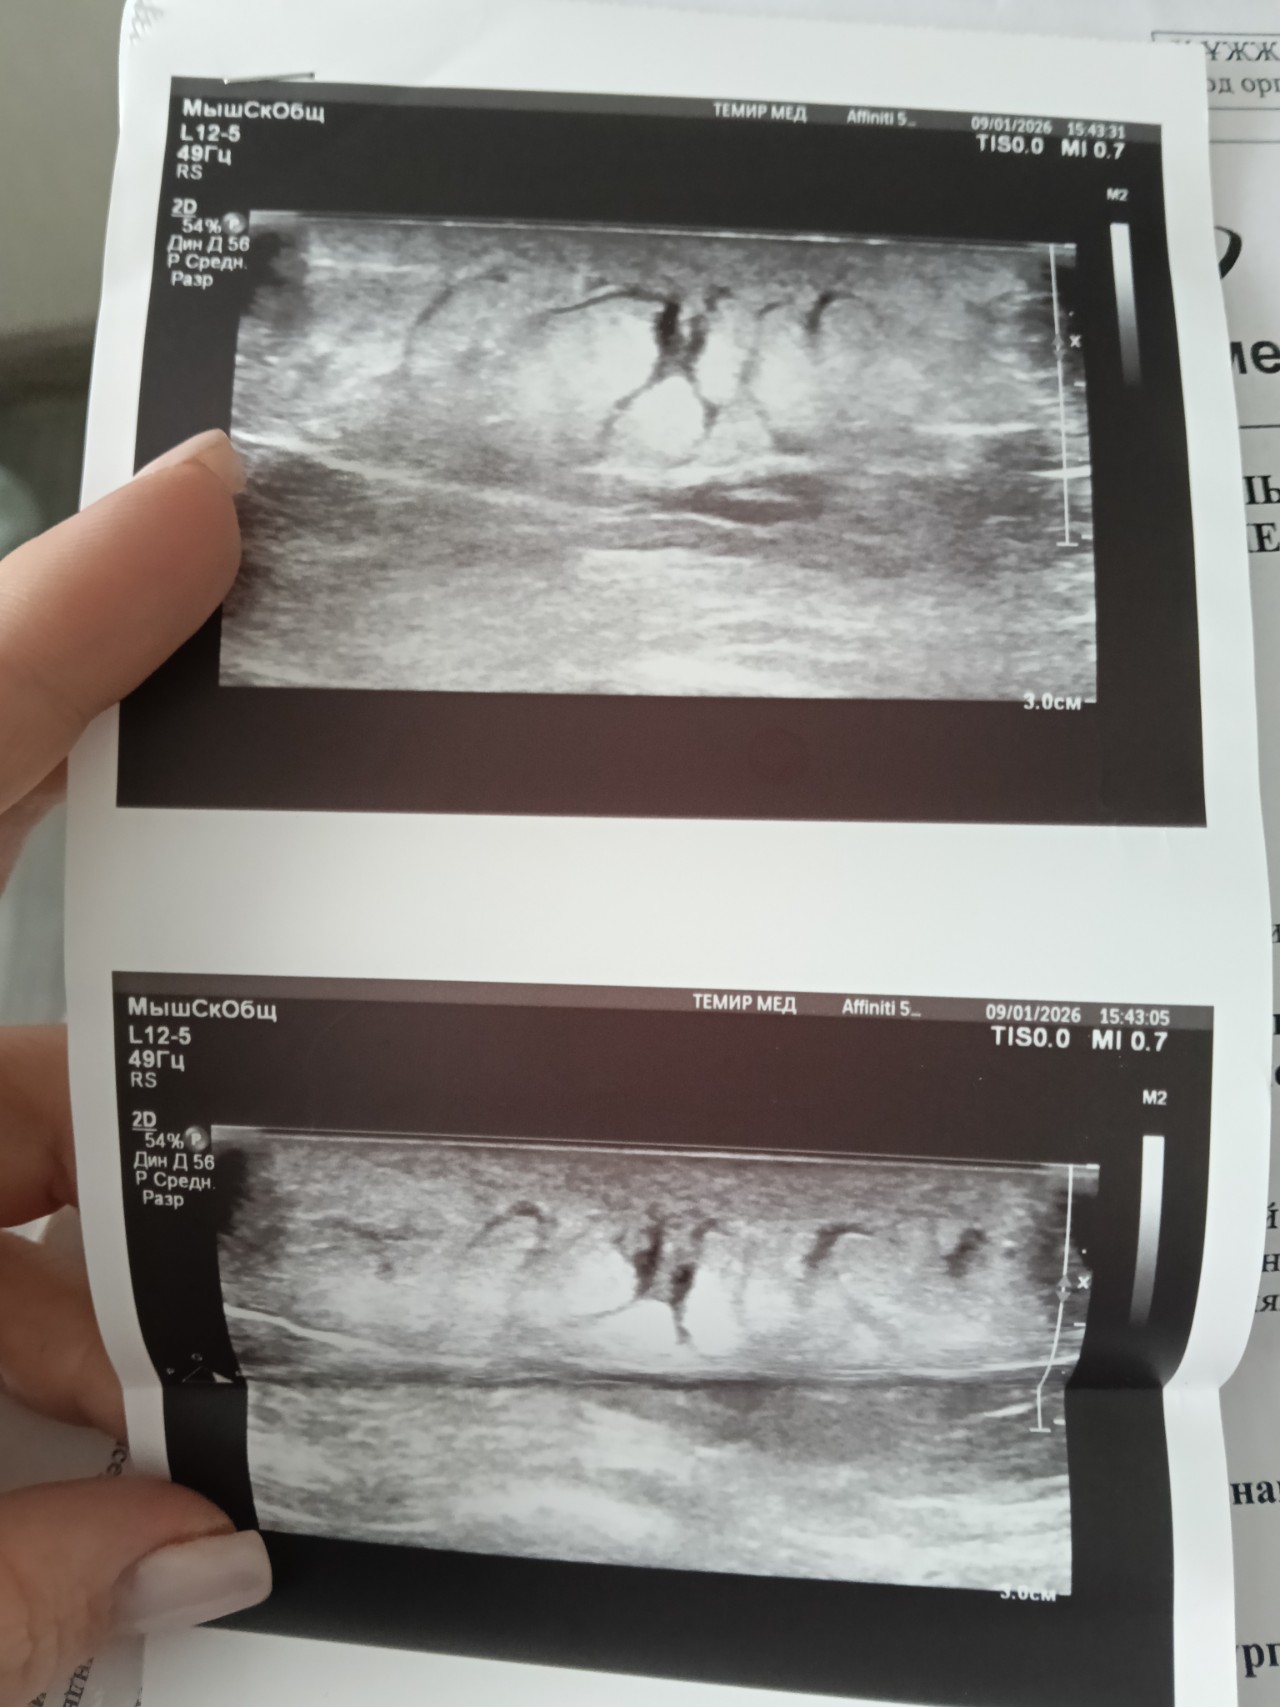

Здравствуйте, в конце декабря нащупала у себя сбоку справа в районе ребер небольшое уплотнение, которое немного зудилось и шелушилось, благополучно о нём забыла, так как больше никаких симптомов не было, в середине января это уплотнение дало о себе знать, покраснело, увеличилось в размере, начало выступать над кожей, горячее на ощупь, обратилась к хирургу, было назначено курс антибиотиков внутримышечно и мазь Вишневского местно, диагноз поставил Подкожный инфильтрат, сходила на УЗИ мягких тканей сказали что образование внутрикожное и подтвердили диагноз хирурга, после начала лечения образование быстро уменьшилось, и в течении этого месяца вообще исчезло, повторно пошла к хирургу он сказал что это уже Липома, пока наблюдать и если будет расти нужно будет удалить.

фото УЗИ тоже прикреплю